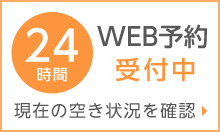

1日~2日で熱が収まってくると、徐々に口の中や手にポツポツが出現!

とくに喉や口蓋(口の上の部分)の奥にたくさんできます。

口の中の他の場所に口内炎ができる。